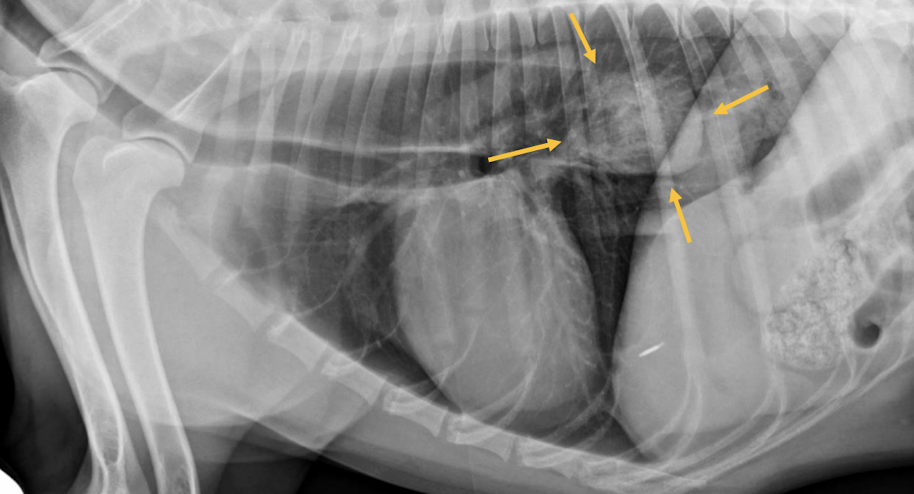

A

Esophageal dilation

Arrow = tracheal stripe